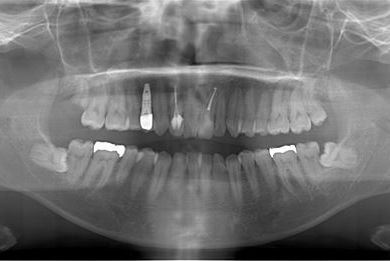

インプラントの症例写真 IMPLANT

インプラント治療+セラミック治療

| 治療内容 | インプラント1本、メタルボンドセラミッククラウン1本、オールセラミッククラウン2本(オールセラミック用土台2本) | ||||||||||||||||||||||||||||||||

| 総治療費 | 703,238円 | ||||||||||||||||||||||||||||||||

| 治療期間 | 1年6ヶ月 |